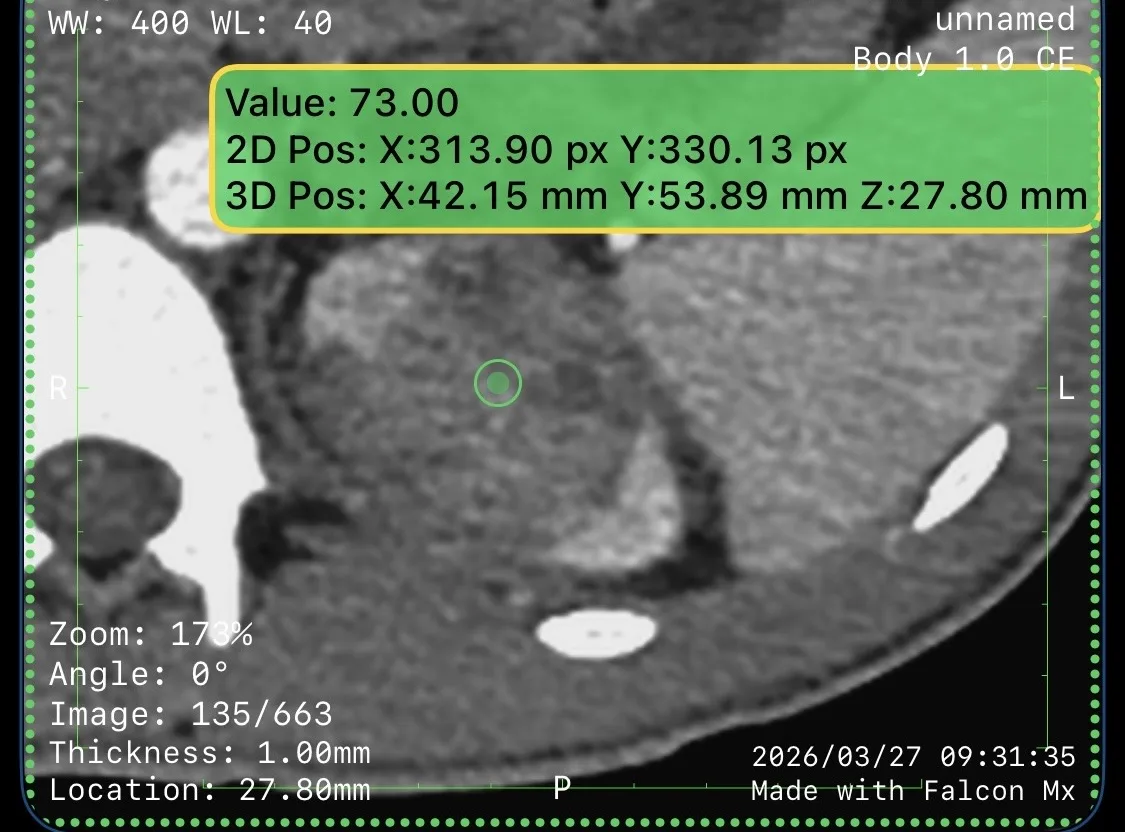

Вот такое нашли у друга… ну ё моё…

Не беспокоило! Три дня назад - макрогематурия.

Красиво получилось. Завтра будем изучать, что там по VI-RADS, результаты доложу. Не переключайтесь.

Сделали мочевой пузырь с контрастом, оказалось три образования в стенке, категория по ви-рац – четвёрка.

То, что по КТ выглядело, как огромное образование, по большей части оказалось кровяным сгустком. Оценить стенку на мрт с контрастом оказалось возможным только благодаря вычитанию, рекомендуем это всем, кто занимается оценкой стадий рака мочевого пузыря на МРТ. Помогает, когда внутри сгустки крови, яркие на нативной T1W.

Вот и думай теперь, что с этим делать. Пузырь удалять?